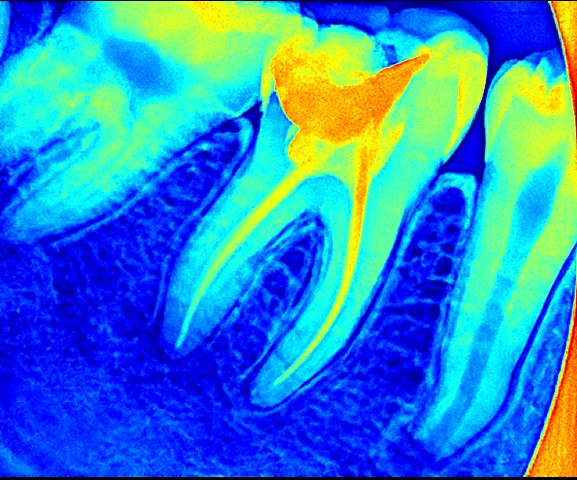

Root canal treatment is a standard dental procedure used to save a tooth that is badly decayed or infected. Inside each tooth is a soft tissue called the pulp, which contains nerves and blood vessels. When this pulp becomes infected due to deep cavities, cracks, or injury,. Consequently, it can cause pain and swelling and may even lead to abscesses if left untreated.

During a root canal, your dentist will carefully remove the infected pulp, clean and disinfect the inside of the tooth, and then fill and seal it with a safe material. The tooth is then usually restored with a crown to protect it and restore its strength and function. Many people worry that root canal treatment is painful. But with modern techniques and local anaesthesia, it is typically no more uncomfortable than getting a filling. Moreover, it relieves pain and helps you keep your natural tooth.